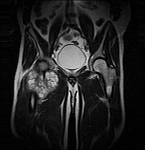

• Extensive reconstructive procedures for the reconstruction of large pelvic bone defects

• Tumor surgery of the musculoskeletal system

• Resection of benign and malignant tumors of the bone and soft tissue